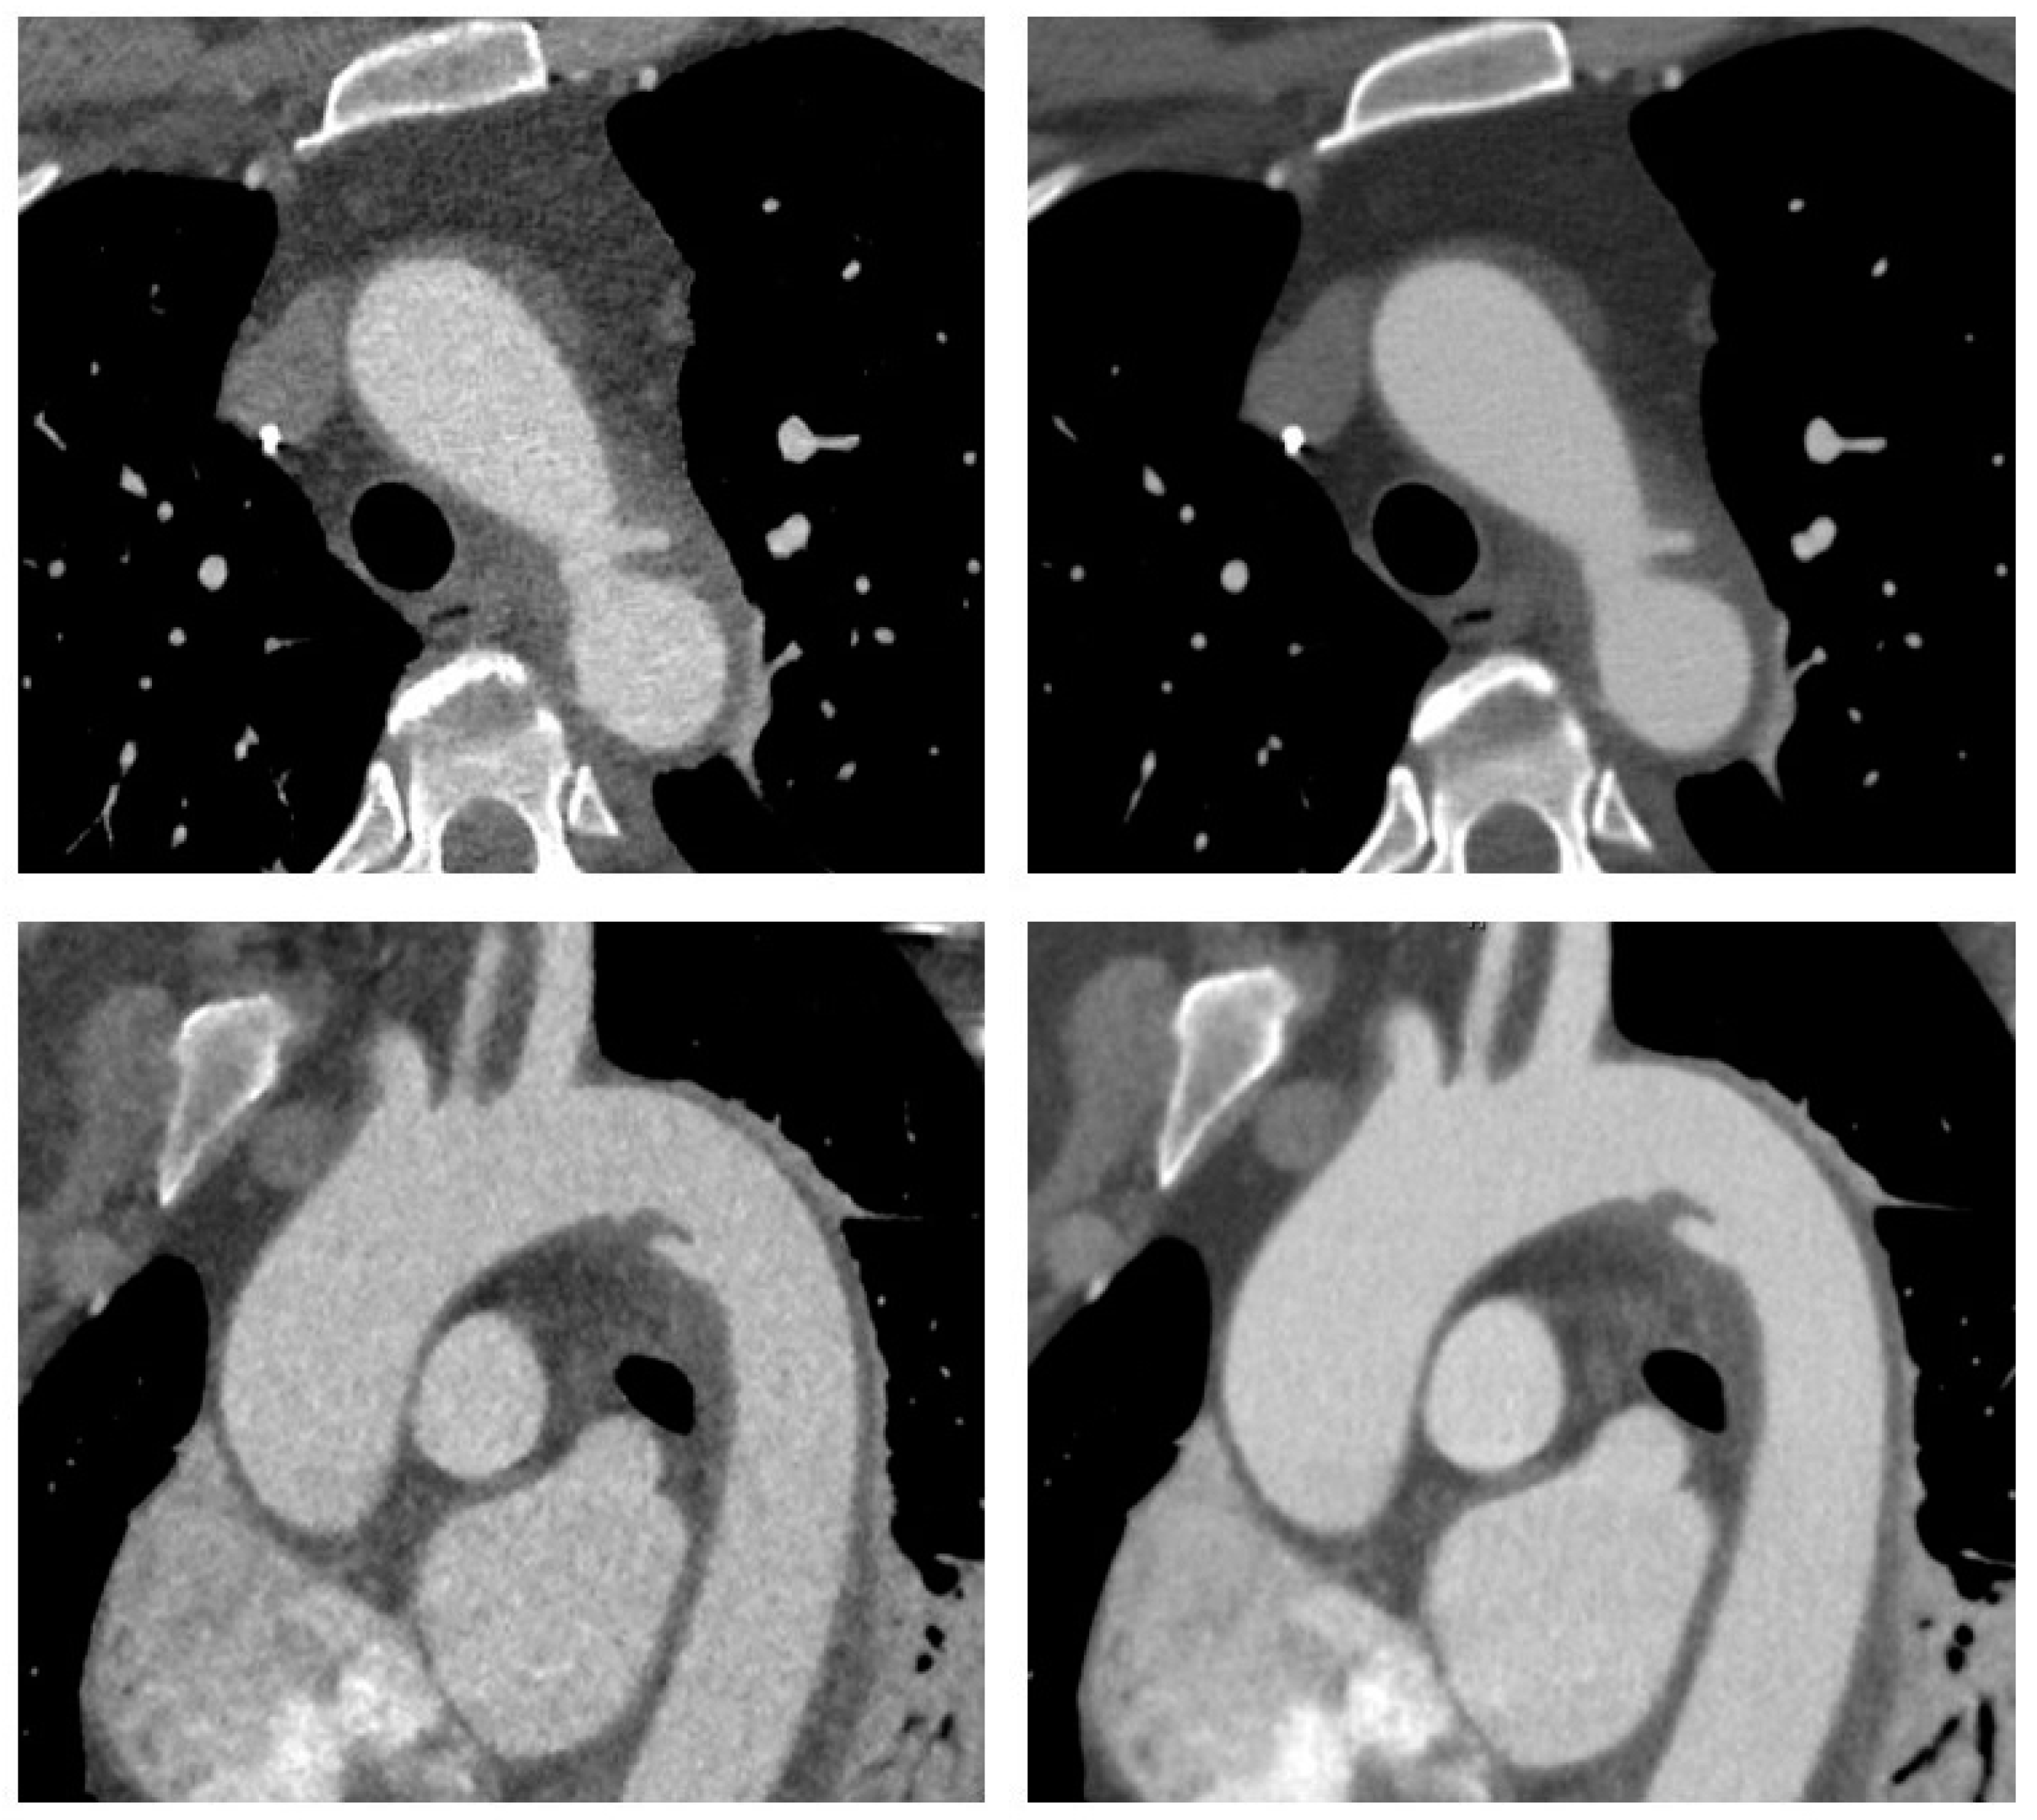

Figure 1.

CT angiography of the aorta in a 54-year old woman involved in a motor vehicle accident. Transverse (upper row) and sagittal oblique (lower row) reconstructions are shown with adaptive statistical iterative reconstruction V (ASIR-V 60%, left) and deep learning-based image reconstruction–high strength (DLIR-H, right). Images demonstrate traumatic injury to the aortic isthmus with adjacent hematoma indicating contained aortic rupture. The patient was hemodynamically stable and was successfully treated with implantation of an aortic stentgraft.